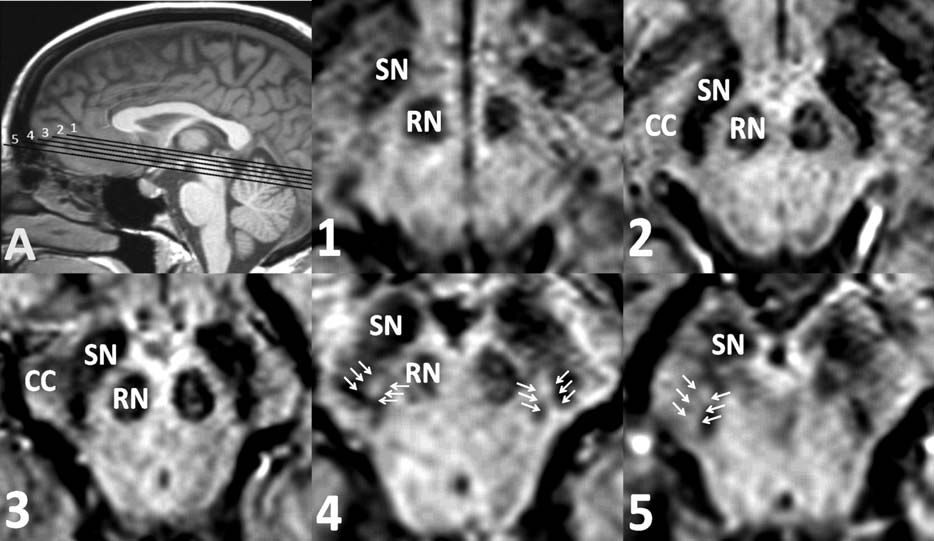

PD 的 MR 表現(xiàn):早期表現(xiàn)往往正常;晚期可出現(xiàn)黑質(zhì)致密部失去正常高信號,邊緣變?yōu)槟:?。黑質(zhì)正常燕尾形態(tài)縮小和喪失。

正常情況下燕尾征-SWI 的顯示:從上至下連續(xù) 1-5 層,黑質(zhì)(SN)出現(xiàn) 5 層,紅核(RN)出現(xiàn) 4 層,黑質(zhì)背外側(cè)部高信號一般位于位于黑質(zhì)的后 1/3,在紅核最后一層或消失的層面出現(xiàn)。

PD、MSA 和 PSP 出現(xiàn)燕尾征-SWI 高信號的消失

燕尾征-SWI 高信號的消失對于鑒別神經(jīng)退行性變和非退行性病變可能具有意義,但是對于鑒別帕金森病與帕金森綜合征還是缺乏準確性的。